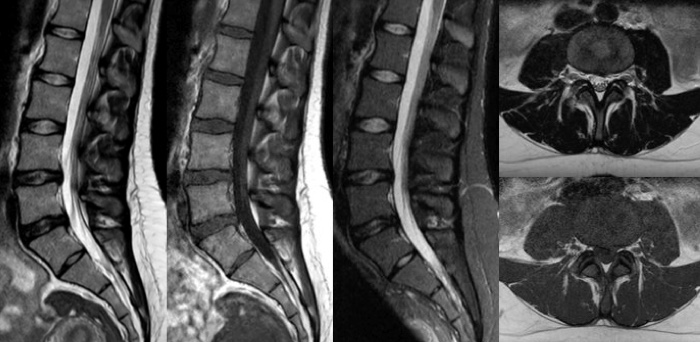

Gracias a Compressed SENSE, gane tiempo y reduzca la duración de las exploraciones hasta en un 50%2 con una calidad de imagen prácticamente igual. Cree imágenes de RM excepcionales con una resolución un 60% superior para un diagnóstico seguro.

Convencional

Compressed SENSE